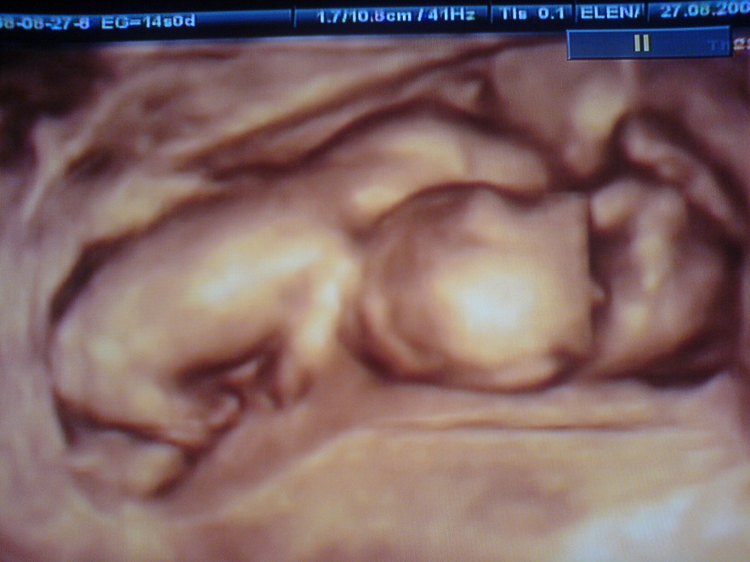

Ultrasonidos 4D: un ultrasonido 4D es similar a un ultrasonido 3D, pero la imagen muestra el movimiento como lo haría un video. Entonces, en una ecografía 4D, vería a su bebé haciendo cosas en tiempo real (como abrir y cerrar los ojos y chuparse el dedo).

– Confirmación del número de bebés en el útero

Las imágenes de embarazos anteriores (por ejemplo, en su ultrasonido de morfología de rutina de 18 a 20 semanas) aparecerán diferentes a la linda cara de bebé con mejillas regordetas que puede haber visto en la televisión o en un artículo de periódico. Los bebés al principio del embarazo no tienen el mismo grado de grasa subcutánea. Esto significa que su bebé se verá menos “lleno” y más esquelético o huesudo en las imágenes 3D/4D. Muchos padres aún disfrutan viendo estas primeras imágenes en 3D/4D, especialmente cuando su bebé se mueve. Estas imágenes también son buenas para obtener ecografías anteriores, ya que muchas mujeres no necesitarán regresar para una ecografía del tercer trimestre.